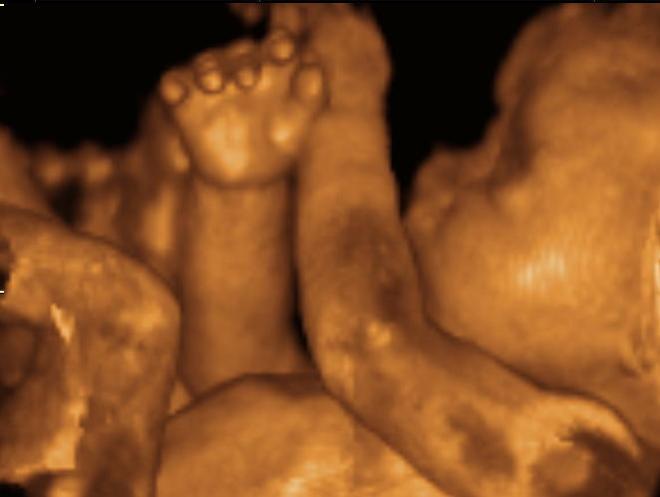

I had seen hundreds of ultrasound images during my short life, but nothing like these.

These were pictures of my son – a tiny baby I have yet to hold or kiss or hug, but a son who I already love just as much as my other three children. There, on the screen, were his eyes, his nose, his fingers, his toes. There was his hair – his hair! And there was his little heart, pumping so fast that I could barely count the beats. On this day he was quite active in the womb, and we enjoyed the show as he seemingly did his best to hide from the nurse. He squirmed and kicked, rolled from side to side, and even opened and closed his mouth. I smiled in wonder and amazement … and then cried tears of joy.

You see, this was our very first ultrasound as a couple. Our first three children were adopted, and although we saw all of them immediately after birth, we never saw them live, in the womb.